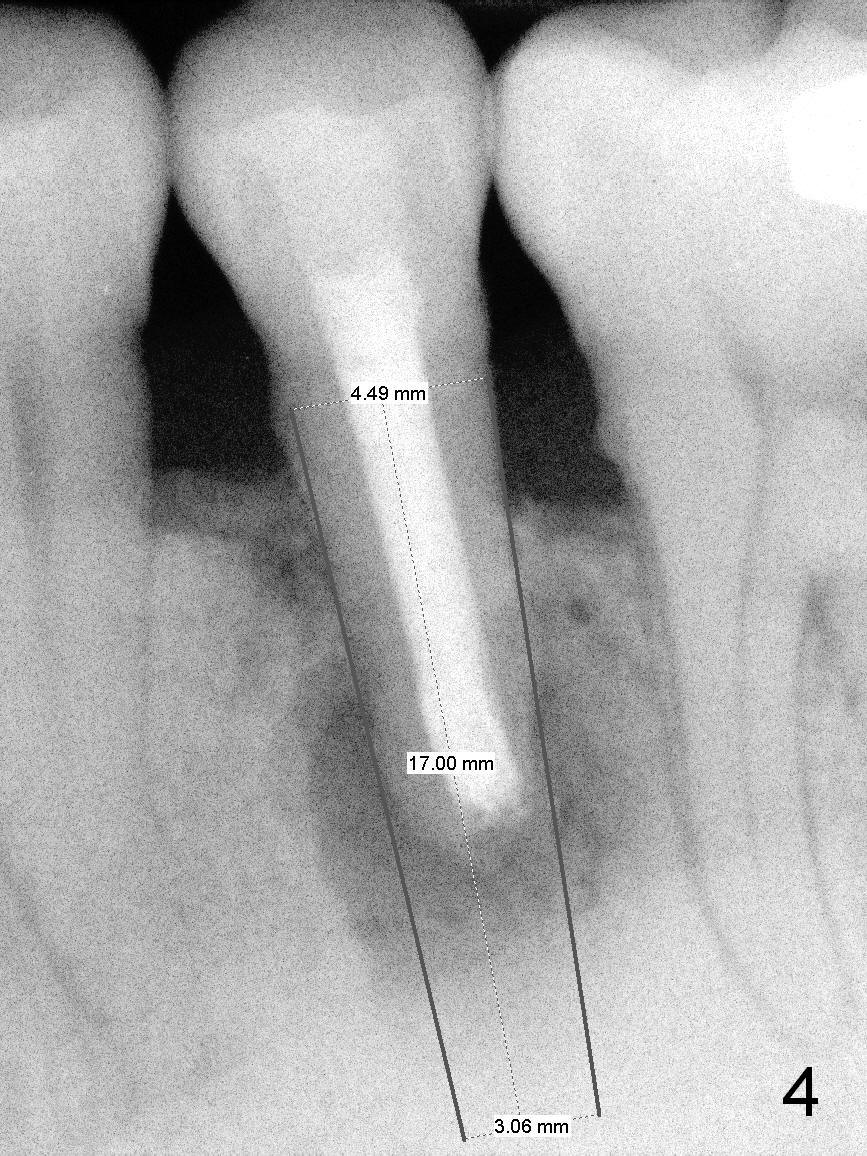

A 45-year-old man (JT) has endo failure at #20 with fenestration (Fig.1,2 black >) and fistula (white <). Insertion of a Gutta Percha at the fistula (Fig. 3 <; PA taken 2 years ago) indicates that the infection is dervied from the apex of the tooth #20. The socket will be soaked with 2% Xylo, 1:50,000 Epinephrine gauze. A 4.5x17 mm tissue-level (Fig.4) or 14 mm bone-level implant is placed as lingual as possible (Fig.5 green). If primary stability is achieved, an abutment is placed (pink). A large piece of resorbable membrane is used to cover the buccal defect (including buccal recession, fenestration and fistula (Fig.6 yellow dashed line). Two small pieces of non-resorbable membrane are placed to cover the gingival recession and the fenestration (Fig.7 white dashed line, buried underneath the edge of the gigniva). Then place bone graft buccally. Place a small piece of gauze (one layer) or plastic (from Tatum implant bag) over the 2nd membrane over the gingival recession and fabricate an immediate provisional. When the acrylic is partially set, remove the gauze or plastic from the provisional. After trimming and polishing, the provisional is cemented to securely keep the 2nd membrane in place. When the wound is healing and the 2nd membrane is stable, trim the buccal extension of the provisional. It is expected that the buccal hard and soft tissue will regenerate over the implant.